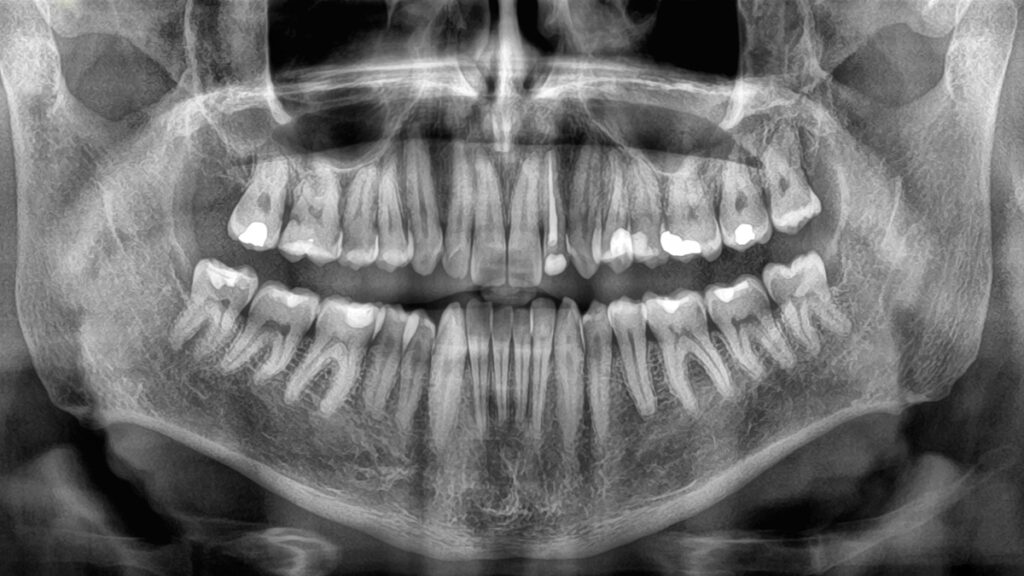

In a groundbreaking study, researchers have found a significant link between the rate of tooth loss in older adults and their risk of mortality. Conducted by a team from Sichuan University in China, the study highlights the critical importance of maintaining good oral health and suggests that rapid tooth loss could serve as a key indicator of underlying health issues.

Previous research has established a connection between having fewer teeth and a higher likelihood of earlier death. However, this new study provides the first comprehensive data on how the speed of tooth loss might influence this association. The research tracked 8,073 elderly individuals over an average of 3.5 years, examining the correlation between the rate of tooth loss and mortality.

The results, published in a recent paper, reveal that a faster progression of tooth loss significantly increased the risk of all-cause mortality among older adults, regardless of their initial number of teeth. This relationship persisted even after accounting for various factors that can affect health outcomes, such as age, sex, education, drinking habits, and exercise levels.

Importantly, the study does not suggest that losing teeth quickly causes death. Instead, it proposes that the health issues leading to tooth loss may also be contributing to a shorter lifespan. Thus, tooth loss could be a valuable indicator for assessing an individual’s overall health and mortality risk.